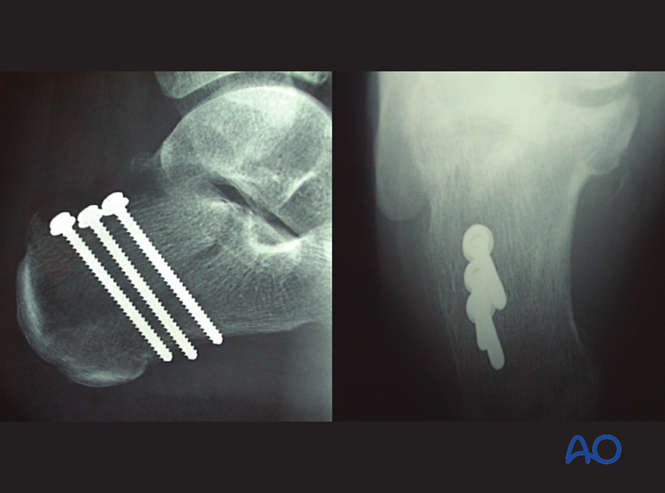

皮质骨拉力螺钉(cortical lag screw)置入

复位后垂直骨折线置入拉力螺钉:

●推荐2-3枚全皮质螺钉,利用跟骨结节厚实跖侧骨皮质增强把持力

●螺钉应置于结节负重区稍前方

●骨质疏松者可加用垫片